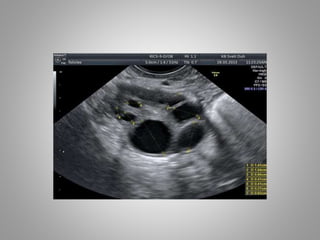

Baseline, prior toinitiating gonadotropin stimulation. Ovary with antral follicles

Stimulation day 5,showingrecruited follicles measuring 10–12mm

Stimulation day 9,showing ovary with growing follicles